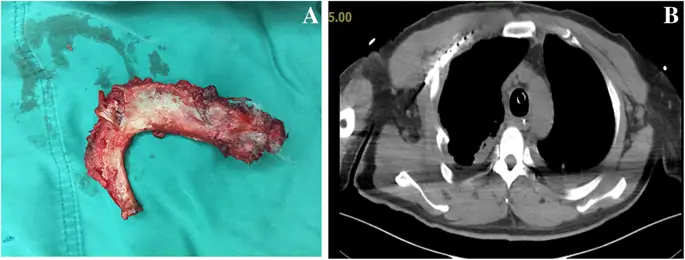

figure4

Правое первое ребро было удалено. б Послеоперационная компьютерная томография, показывающая целостность задней стенки трахеи

Письменное информированное согласие на публикацию данного дела было получено от пациента. Мужчина 56 лет (рост 165 см; вес 70 кг) без значительного медицинского анамнеза обратился в отделение неотложной помощи с жалобами на боль в правой груди, застой в груди и одышку после получения тупой травмы правой груди. Его жизненные показатели были следующими: частота сердечных сокращений (ЧСС), 91 уд / мин; частота дыхания (ОР), 34 вдоха / мин; артериальное давление (АД), 108/71 мм рт.ст.; и начальная пульсовая оксиметрия насыщения (SpO 2) 85%. Газ артериальной крови: рН 7, 35, ПаСО 2 47 мм рт. Ст. И ПаО 2 49 мм рт. Хрипящая грудь и парадоксальное дыхание были очевидны. Значительная подкожная эмфизема в области шеи и передней части груди была диагностирована с выраженным крепитацией. Компьютерная томография (КТ) показала массивную подкожную эмфизему, пневмомедиастинум, множественные переломы ребер, двусторонний гемопневмоторакс и компрессионный пневмоторакс (рис. 1 а и б). Было замечено смещение сочленения грудины, и стернальная часть правого первого ребра проникла через заднюю стенку трахеи над килем (рис. 2). Грудная трубка была вставлена для декомпрессии пневмотораксов и гемопневмоторакса, и проблемы с дыханием были облегчены. К сожалению, быстрое ухудшение подкожной эмфиземы указывало на постоянную утечку воздуха через разрыв через 3 часа. У пациента развился респираторный дистресс и он стал гемодинамически нестабильным. Эмерджентная КТ показала, что правое первое ребро проникло через заднюю стенку трахеи примерно на 6 см ниже голосовой щели и на 6 см выше киля (рис. 3а). Первое ребро разделило трахею на две части: 5, 3 мм в диаметре слева и 6, 6 мм справа (рис. 3, б и в). Пациент был быстро переведен в операционную. Он был взволнован, при дыхательной недостаточности и его жизненные показатели были: ЧСС 108 уд / мин; 30 вдохов в минуту; BP 90/58 мм рт.ст. и SpO 2 80%. Мы поддерживали гемодинамическую стабильность с помощью внутривенного фенилэфрина. Фиброоптический бронхоскоп был сразу же доступен с эндотрахеальными трубками разных размеров. Общая анестезия была индуцирована мидазоламом 2 мг, фентанилом 0, 05 мг и 2% ~ 5% севофлюраном при сохранении спонтанной вентиляции. Стерильный гибкий волоконно-оптический бронхоскоп, загруженный 5, 5 мм эндотрахеальной трубкой (наружный диаметр 7, 3 мм), идентифицировал разрыв трахеи, и эндотрахеальная трубка была продвинута дистально мимо места разрыва. Он самопроизвольно дышал с фракцией вдыхаемого кислорода 100%, дыхательным объемом 330 мл, частотой 30, SpO 2 95% и парциальным давлением конечного прилива двуокиси углерода (PetCO 2) 40 мм рт. Глубина анестезии поддерживалась до достижения показателя биспектрального индекса 40-60. Хирургическая бригада открыла грудную полость, чтобы обнажить правое первое ребро, а правое первое ребро было удалено примерно через 30 минут (рис. 4а). Эндотрахеальную трубку диаметром 7, 5 мм затем заменяли и располагали дистально до разрыва под руководством гибкой бронхоскопии. После подтверждения расположения эндотрахеальной трубки внутривенно вводили цисатракурий 14 мг и фентанил 0, 15 мг. Пациенту была проведена искусственная вентиляция легких с интервалом положительной вентиляции. Респираторные параметры были следующими: фракция вдыхаемого кислорода 60%, дыхательный объем 550 мл, частота 12, пиковое давление в дыхательных путях 22 см H 2 O, SpO 2 98% и PetCO 2 38 мм рт. Непосредственное хирургическое восстановление разрыва трахеи было успешным, и он был переведен в отделение интенсивной терапии. В отделении интенсивной терапии ему управляли на вентиляторе с синхронизированной прерывистой принудительной вентиляцией и постоянным положительным давлением в дыхательных путях. Для улучшения легочной функции на 5-й день после первой операции были выполнены плановые хирургические операции по восстановлению перелома грудины, множественных переломов ребер и гемопневмоторакса под общей анестезией, а у пациента был экстубирован на 7-й день после операции. Повторная КТ продемонстрировала целостность стенки трахеи (рис. 4 б). Комплексная реабилитация проводилась в течение 2 недель, и он был выписан домой в послеоперационный день 41.